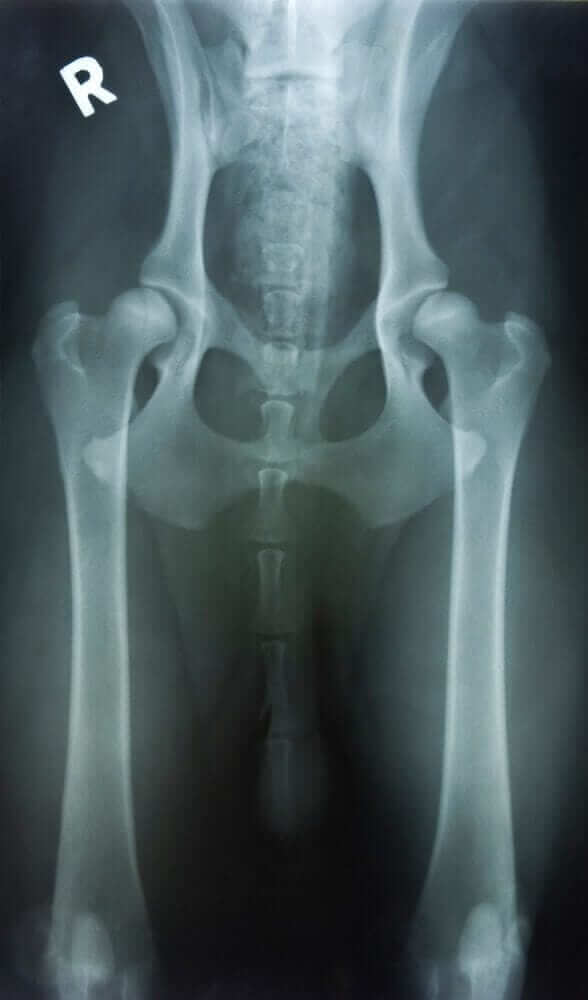

Arthritis is a degenerative condition that usually occurs over time as the pet or dog ages. It is similar to a snowball rolling down a hill. Once it gets started, it is often hard to stop. Ideally, your goal is to step in early, even before the condition develops. You want to be proactive than reactive. By the time your dog has joint pain and evidence of arthritis on the radiographs, it means the condition has already progressed. You want to intervene before this stage, especially in the larger breed dogs that are more prone to arthritis of the hip, knee, and back region.